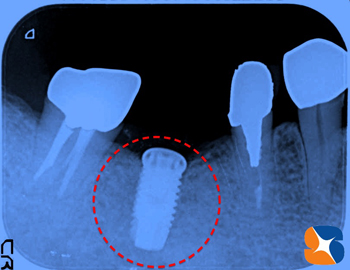

(1) 人工の根を歯茎にさす手術→(3ヶ月後)→(2) 歯肉を強化する手術→(1ヶ月後)→(3) 型取り→(1ヶ月後)→(4) 完成

治療計画5ヶ月間